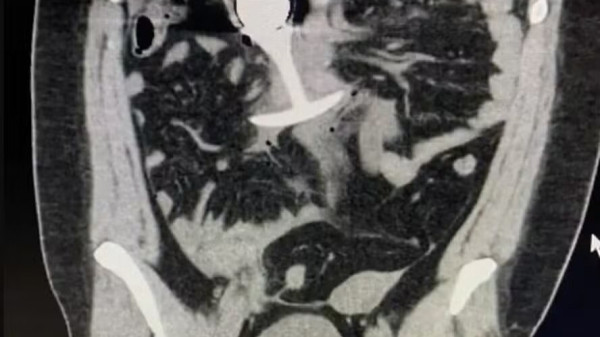

Apesar da preocupação gerada, ainda há falta de clareza sobre o nível exato de lesões sofridas pela paciente, que não retornou os contatos médicos subsequentes para acompanhamento. O caso gerou debate nas redes sociais sobre a importância de seguir protocolos rigorosos antes de realizar exames de RM. Além disso, especialistas alertam para que, durante o procedimento, nenhum objeto metálico esteja no corpo do paciente, como brinquedos sexuais, próteses ou fragmentos metálicos.